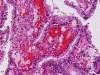

On FNA with Pap stain, clusters of cells with a papillary structure are present (Panel A). A delicate fibrovascular core can be seen at the center (arrow in Panel B). In higher magnification, two population of cells are present. While one of the population appears as solid sheets of polygonal epithelial cells with increased nuclear cytoplasmic ratio and distinct cell border (arrow head in Panel C), there are also many cells with distinctly foamy cytoplasm, lower nuclear cytoplasmic ratio and bland nuclei, and indistinct cell border (arrow head in Panel C). The foamy cells are most consistent with foamy macrophages. A distinct nucleoli is present in the epithelial cells (Panel D). The papillary morphology is well demonstrated in the cell block (Panel E, F, and G). Characteristically, the papillary structures are formed by a central core of foamy macrophages and covered by a epithelial cells. The epithelial cells but not the foamy macrophages are immunoreactive for CD10, AMACR, and CK7 (Panel H, I, and J).

Histologically, the proportion of papillary growth can vary. While papillary growth can be the dominant pattern in some tumor, tumors composed of predominantly solid growth areas can be seen. The papillary growth has fine, delicate fibrovascular cores. Foamy macrophages are usually abundant and they are usually wonderful diagnostic suggestions. However, it should be noticed that areas that lack foamy macrophages can occur. This is particularly important when the specimen is small such as FNA specimens. The tumor cells fall into two major cytologic types. Type 1 tumors cells vary from small cells with inconspicuous pale cytoplasm and small, uniform, spherical nuclei with small or invisible nucleoli. Type 2 tumor cells are larger cells with abundant eosinophilic cytoplasm and large, spherical nuclei, prominent nucleoli and pseudostratified arrangement. Mixed pattern within the same tumor is not uncommon. 1, 2, 4, 5